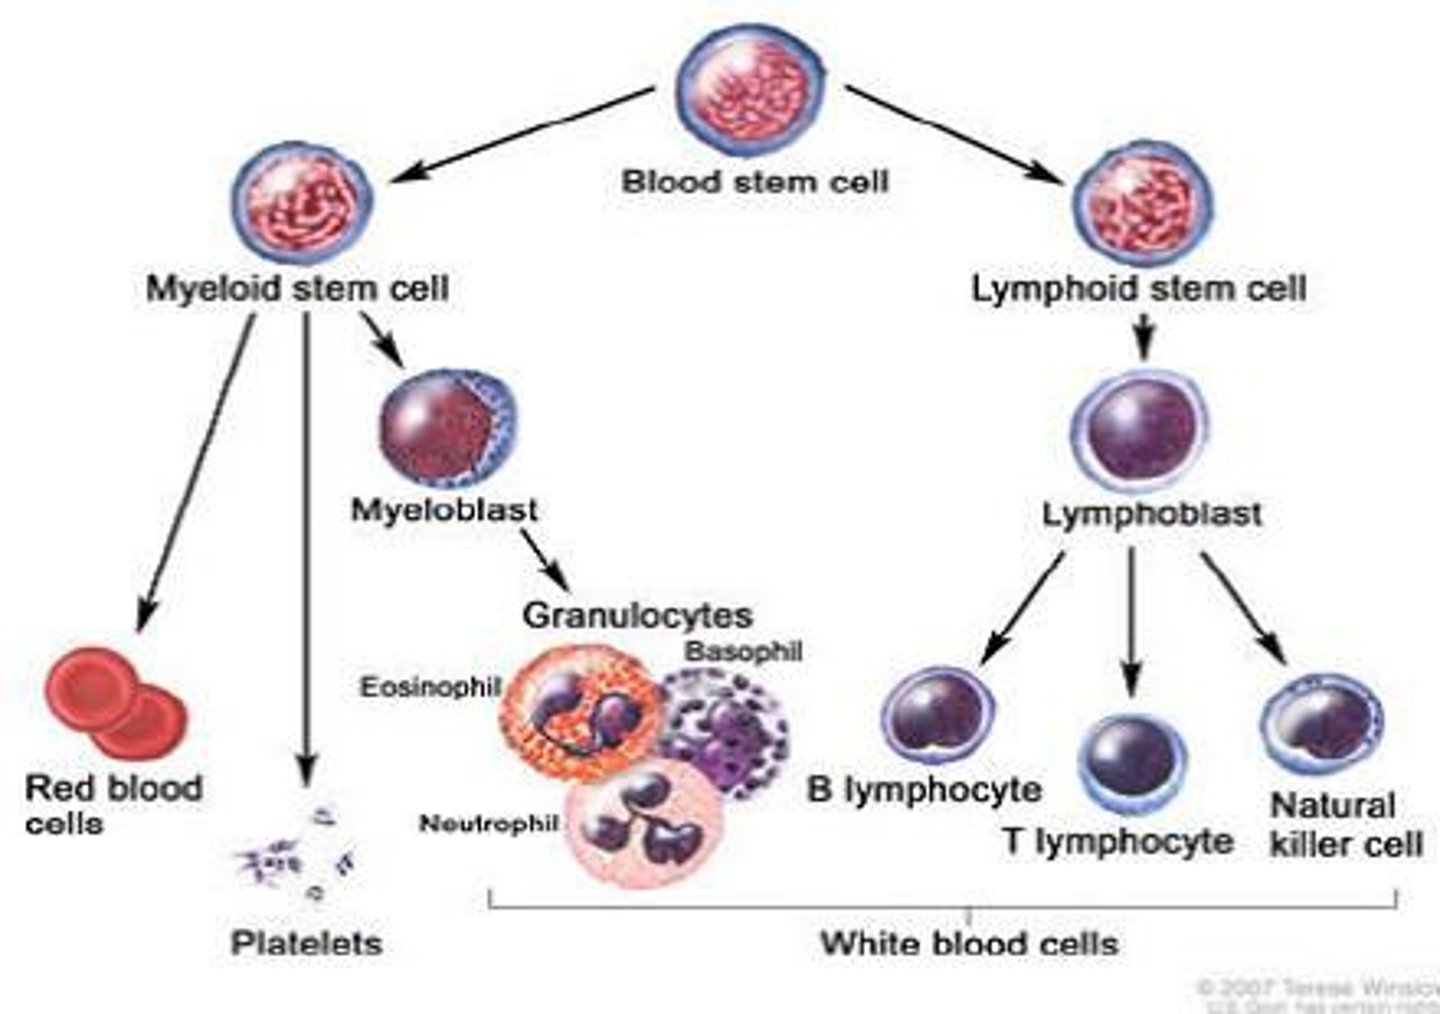

Hematopoiesis

The formation of blood cells from stem cells in the bone marrow

What are pluripotent cells?

Stem cells that can differentiate into each of the different types of blood cells

Lymphoid stem cell

Differentiates into the 3 types of lymphocytes (T cells, B cells, NK cells)

Myeloid stem cell

Differentiates into erythrocytes/platelets, and granulocytes/monocytes

B cells

A type of lymphocyte that is created in the bone marrow; creates antibodies that isolate and destroy pathogens

T cells

A type of lymphocyte that is created in the thymus; produce substances that attack infected cells in the body

Natural Killer (NK) cells

A type of lymphocyte found in the blood/lymph nodes/spleen --> they kill cancer cells and cells infected with viruses